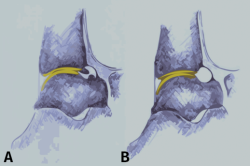

El dolor relacionado con el pinzamiento del tobillo anterior de tipo óseo está probablemente causado por la inflamación de los tejidos blandos (ligamentos, tendones), que se hallan comprimidos por los osteofitos del astrágalo y/o la tibia durante las fuerzas de dorsiflexión (Figura 1)(9,10,11). Existen varias teorías sobre la posible etiología de la formación de osteofitos que producen el síndrome doloroso de pinzamiento del tobillo anterior(12), principalmente basadas en factores mecánicos, inestabilidad crónica del tobillo, microtraumatismo recurrente y/o tracción(1,3,8,13).

Figura 1. Vista de pinzamiento óseo anterior por osteofitos. El tejido sinovial inflamado se comprime entre los osteofitos del astrágalo y la tibia durante la flexión dorsal forzada, lo que probablemente causa el dolor relacionado con el pinzamiento óseo en estos procesos.

La planificación preoperatoria debe centrarse, como hemos señalado, en una correcta diferenciación entre el pinzamiento por lesión de tejidos óseos y blandos, ya que ello puede ser en ocasiones difícil de realizar bajo la visualización artroscópica. Además, como hemos manifestado también, los osteofitos podrían estar cubiertos por tejido cicatricial y/o sinovial inflamatorio, siendo difíciles de detectar y conduciendo, el no resecarlos adecuadamente, a peores resultados quirúrgicos(4,29,30). Es conocido que la identificación preoperatoria de los osteofitos se asocia con mejores resultados, siendo igualmente importante realizar una resección completa(15,19,31). La Figura 3 ofrece una visión general de la anatomía normal de la articulación del tobillo.

Figura 3. Visión lateral de un tobillo que muestra la zona de cartílago anterior de la tibia y la inserción de la cápsula. A: los osteofitos están a nivel distal de la tibia y en talus; B: anatomía tras resecar los osteofitos.